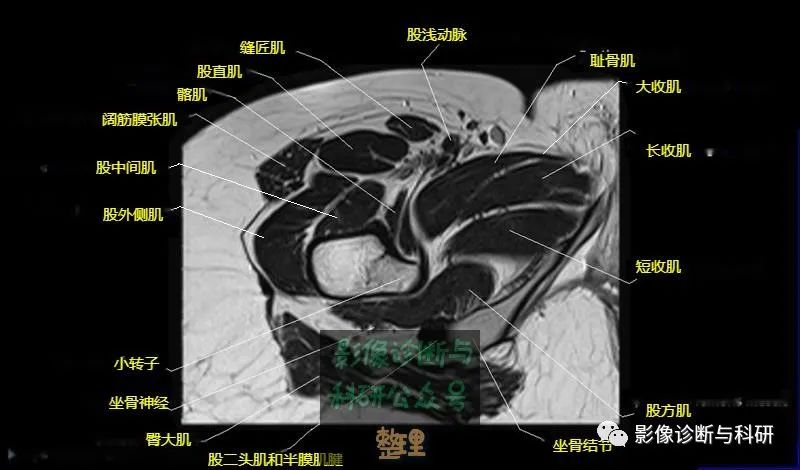

髋关节MR轴位详细标注

大腿肌配布于股骨周围,分前、后和内侧三群

前群

位于大腿前面,有缝匠肌和股四头肌。

内侧群

位于大腿内侧,共5块,其中股薄肌位于最内侧;另4块分三层,浅层靠外上方为为耻骨肌,下方为肌长收肌。长收肌深面是第二层的肌短收肌。第三层是强有力的大收肌。这一群肌均起自耻骨支和坐骨支,除股薄肌止于胫骨上端内侧外,其余各肌都抵止在股骨粗线。

后群

位于股骨后方,包括股二头肌、半腱肌和半膜肌。